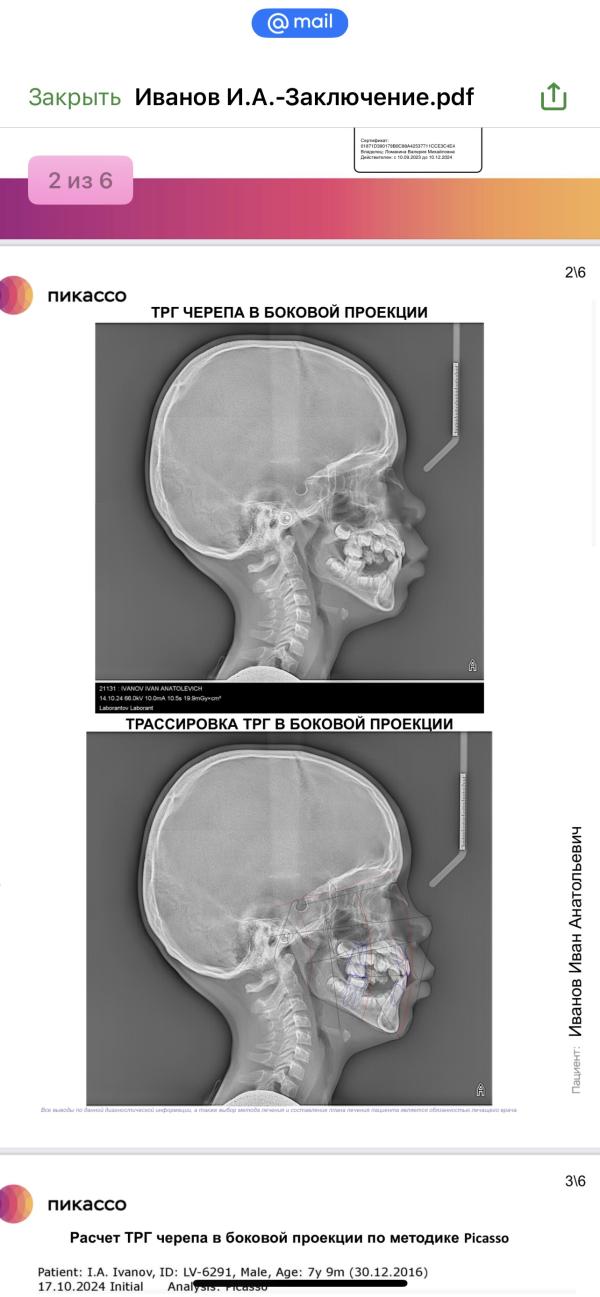

Пошли к ортодонту со снимками и описанием , там на низ сказали ставить капу - чтоб в дырки для будущих коренных челюсть не уехала - ну это понятно ( кстати , в бесплатной клинике на десятку посчитали )., а вот верх .. надо систему ставить , но она только на пятерки , которые еще не укрепились , да и вообще не факт что смогут именно на них . Да еще и передние лишние в дёснах мешают . Поехали в Раухфуса на консультацию , там дали направление на плановую операцию по удалению , внимание , НА АПРЕЛЬ 2026 года !!